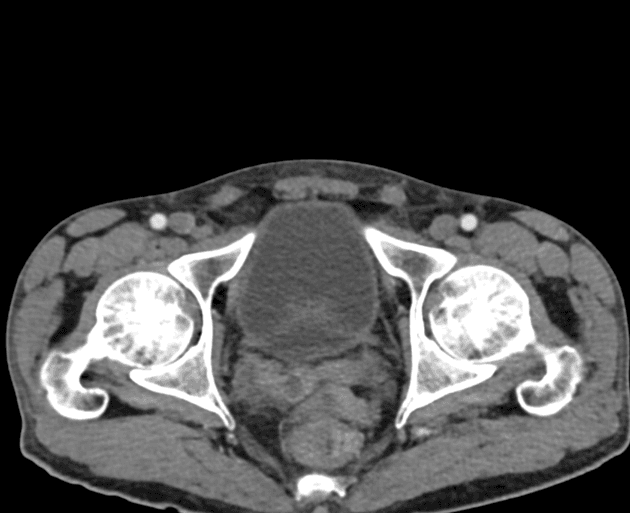

Đau vùng chậu kèm cảm giác khó chịu. Các khối dạng nang vùng chậu trên siêu âm.

Nhiều tổn thương phần phụ dạng nang-đặc hai bên vùng chậu với bờ không đều và tín hiệu hỗn hợp tăng trên T2/giảm trên T1; phần đặc ngoại vi tăng quang sau tiêm. Tổn thương lớn nhất: 65x41 mm (phải), 39x36 mm (trái). Ống dẫn trứng giãn ngoằn ngoèo chứa thành phần hoại tử (21 mm phải, 20 mm trái). Thay đổi dạng nốt viêm và dính trong khoang chậu; mất một phần đường bờ tử cung. Dày dạng nốt nhỏ lan tỏa của mạc nối lớn tạo hình ảnh bánh mạc nối giả. Tổn thương phần phụ trái xâm lấn quai hồi tràng lân cận, biểu hiện giảm tín hiệu T2, hạn chế khuếch tán và tăng quang mạnh; dày đến 11mm, kéo dài khoảng 15cm. Các quai hồi tràng dính nhau nhưng không giãn hay tắc mạch. Tử cung hai sừng hoặc có vách ngăn bán phần. Cơ tử cung, nội mạc tử cung, cổ tử cung và buồng trứng bình thường.

Lao vùng chậu - phúc mạc

- "Lao vùng chậu có thể mô phỏng bệnh lý ác tính buồng trứng trên hình ảnh do các khối dạng nang-đặc và dày mạc nối."

- "Ống dẫn trứng giãn với thành phần hoại tử (viêm ống dẫn trứng) là những chỉ số gợi ý mạnh mẽ về lao."

- "Bánh mạc nối giả và dày mạc nối dạng nốt nhỏ là những đặc điểm đặc trưng của tổn thương phúc mạc."